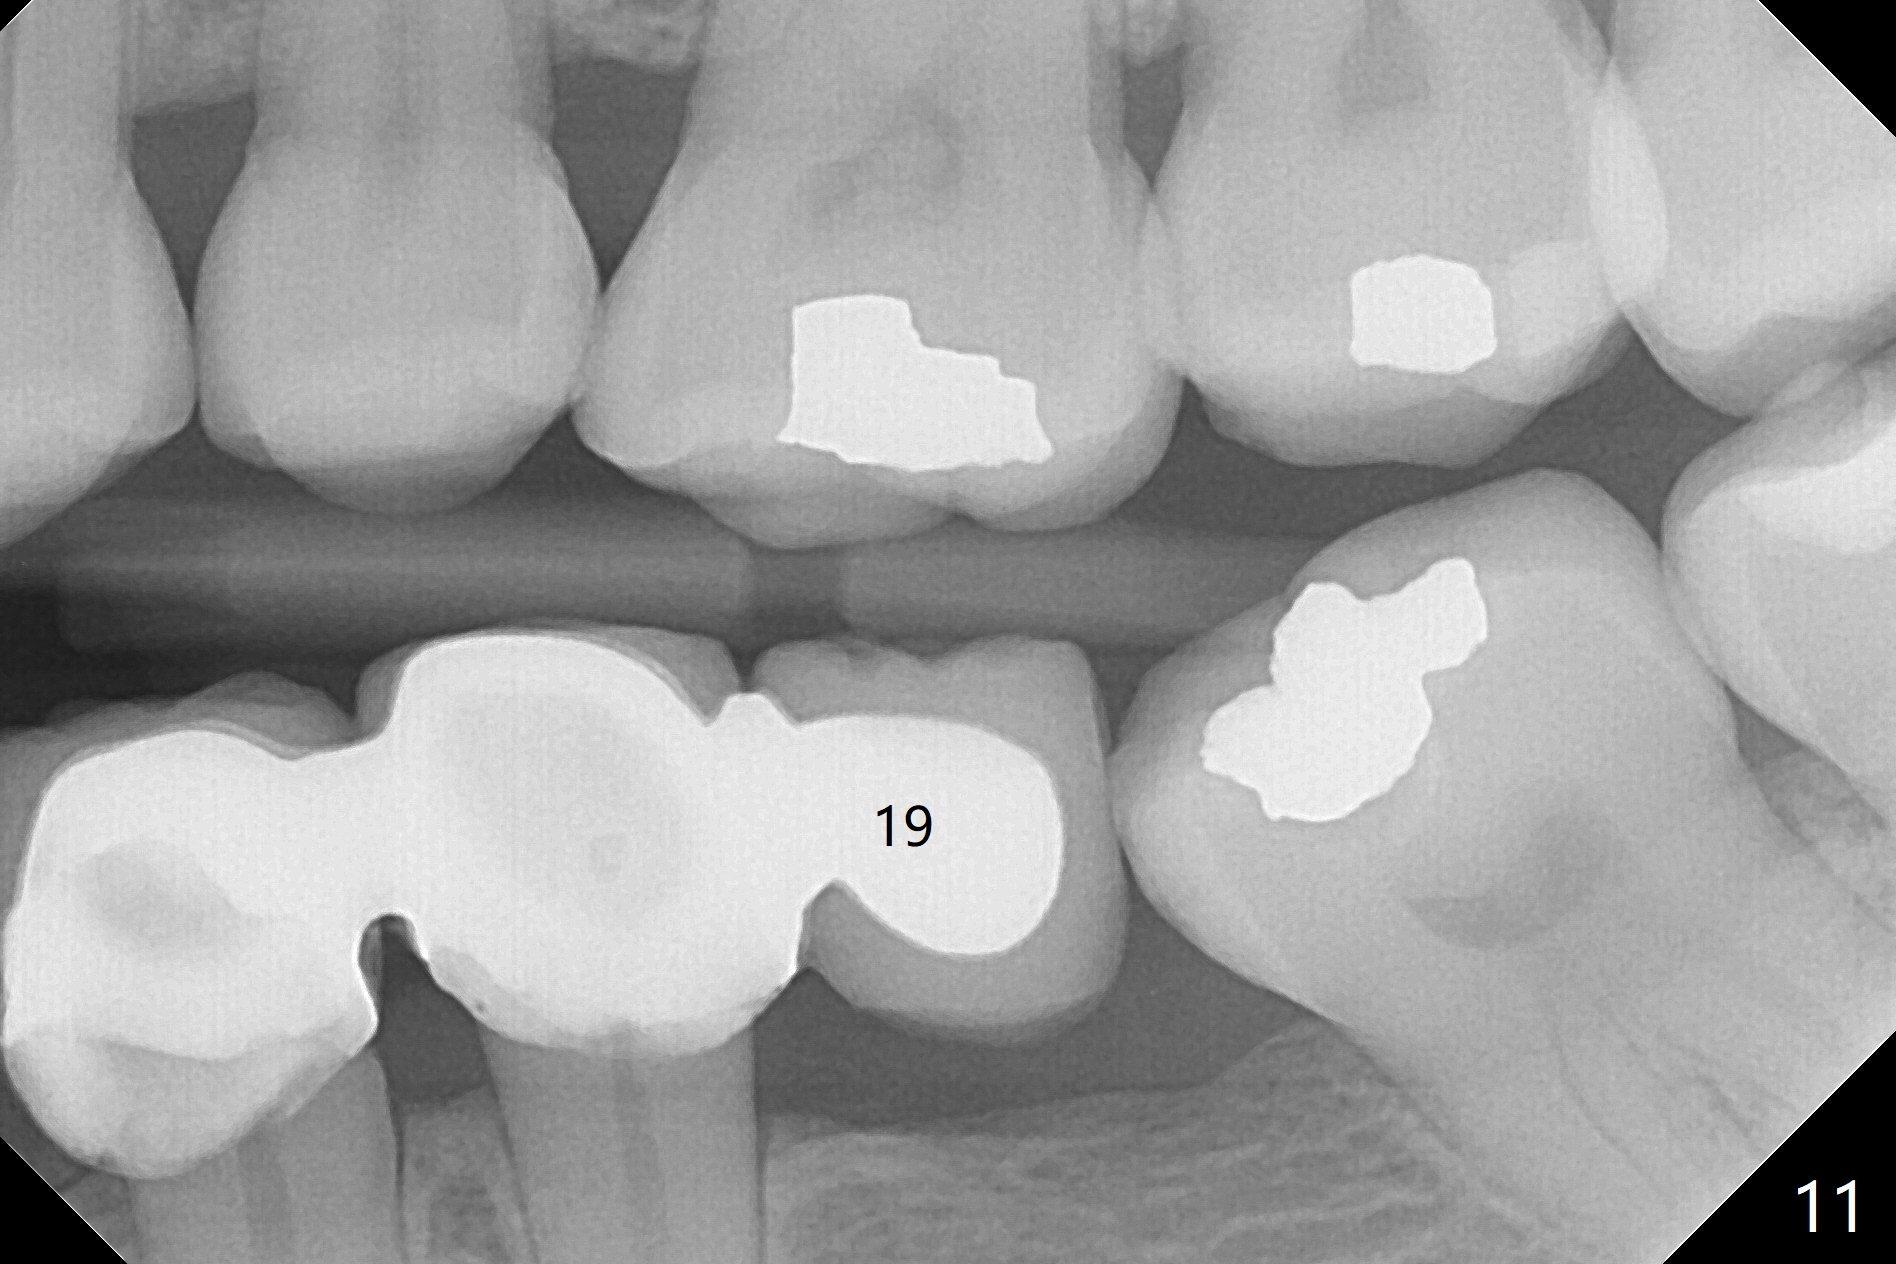

A preop photo shows different shape of pontics at #30 and 31 (Fig.1 <), suggesting different width of the edentulous ridge.  Two of 8 mm parallel pins are inserted for position and trajectory (Fig.2 (red dashed line: the superior border of the Inferior Alveolar Canal).  When they are removed from the osteotomy sites, the narrow ridge at #30 is shown (Fig.3).  A 3x12 mm 1-piece implant is placed at #30, while a 4.5x10 mm 2-piece one at #31 (Fig.4,5).  It appears that it is necessary to place an implant at #32, since the tooth #1 is present (Fig.5).  The suggestion is rejected by the patient due to finance.  After extraction of the tooth #32 and insertion of collagen plug, an immediate splinted provisional is fabricated to cover the #32 socket as well (Fig.6).  The provisional is modified (to remove the portion that covers #32 socket) 3-4 weeks postop.

The patient returns for final restoration 3 months postop; bone resorption around the 1-piece implant is minimal (Fig.7).  The definitive restoration is also splinted.  The latter is further justified when the implant at #30 is found to be distal prior to cementation (Fig.8 *).  It appears that implant spacing at the root level is more critical than parallelism, as compared to Fig.7.  Let us improve this aspect.  Bone loss around the implants remains minimal 7 months post cementation (Fig.9).  It is the same 1 year 8 months post cementation (Fig.10), as compared to a cantilever FPD on the other side (Fig.11).  The bone density around the implants at #30 and 31 increases 2 year 8 months post cementation (Fig.12).